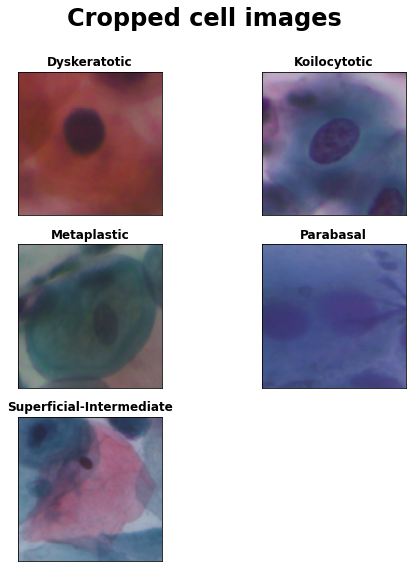

Visualize cropped images

The data set also contains cropped images, which only contain single cells that were extracted after image segmentation. We will use those cropped cell images for training the deep learning classifier.

The SIPaKMeD data set https://www.cs.uoi.gr/~marina/sipakmed.html consists of 4049 images of isolated cells that have been manually cropped from 966 cluster cell images of Pap smear slides. These images were acquired through a CCD camera adapted to an optical microscope. The cell images are divided into five categories containing normal, abnormal and benign cells (descriptions taken from the SIPaKMeD website ):

1. Superficial-Intermediate cells constitute the majority of the cells found in a Pap test. Usually they are flat with round, oval or polygonal shape cytoplasm stains mostly eosinophilic or cyanophilic. They contain a central pycnotic nucleus. They have well defined, large polygonal cytoplasm and easily recognized nuclear limits (small pycnotic in the superficial and vesicular nuclei in intermediate cells). These type of cells show the characteristics morphological changes (koilocytic atypia) due to more severe lessions.

2. Parabasal cells are immature squamous cells and they are the smallest epithelial cells seen on a typical vaginal smear. The cytoplasm is generally cyanophilic and they usually contain a large vesicular nucleus. It must be noted that parabasal cells have similar morphological characteristic with the cells identified as metaplastic cells and it is difficult to be distinguished from them.

3. Koilocytotic cells correspond most commonly in mature squamous cells (intermediate and superficial) and some times in metaplastic type koilocytotic cells. They appear most often cyanophilic, very lightly stained and they are characterized by a large perinuclear cavity. The periphery of the cytoplasm is very dense stained. The nuclei of koilocytes are usually enlarged, eccentrically located, hyperchromatic and exhibit irregularity of the nuclear membrane contour.

4. Dysketarotic cells are squamous cells which undergone premature abnormal keratinization within individual cells or more often in three-dimensional clusters. They exhibit a brilliant orangeophilic cytoplasm. They are characterized by the presence of vesicular nuclei, identical to the nuclei of koilcytotic cells. In many cases there are binucleated and/or multinucleated cells.

5. Metaplastic Cells are in essence small or large parabasal-type cells with prominent cellular borders, often exhibiting eccentric nuclei and sometimes containing a large intracellular vacuole. The staining in the center portion is usually light brown and it often differs from that in the marginal portion. Also, there is essentially a darker-stained cytoplasm and they exhibit great uniformity of size and shape compared to the parabasal cells, as their characteristic is the well defined, almost round shape of cytoplasm.